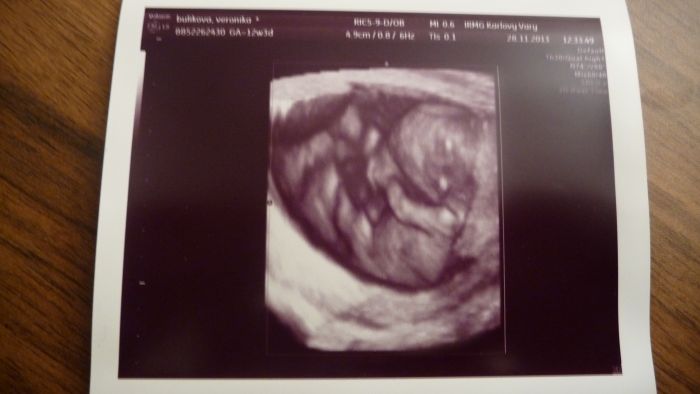

jeste pridavam foto nasi princezny a dneska jsem se rozhodla a bude se jmenovat Ellen.....tata bude mit radost az na kost a moje sestra taky, ti dva totiz jmeno vymysleli

Marti, krásná fotečka!

[397014] Martasku a v kolikatem jsi? Ja jsem 12+4 a nemam z dneska tak hezkou fotku. 3D úplne nepoznatelny a normální docela pěkný, ale třeba nozicky nejdou v podstatě videt.

Ahojte těhulky, tak jsem dnes byla na screeningu, KONEČNĚ... ALE... čekám prý flegmatické spací mimčo

Doktor do mě bušil, musel mě vyšetřit vaginálně a mímo pořád spinkalo, vždy se jen zavrtělo, jako že nech mě a zase spinkalo. Vypadá prý vše ok, krev budou volat jen pokud něco objeví. Tak snad to bude také OK. Jinak máme 4,64 cm a Dr. mi řekl, že nejspíš nebudu v tom 12tt ale asi v 10tt. Tak nevím. Posune se mi TP, tak příští pondělí jdu na kontrolu k mé Dr. tak písnu. Srdíčko jsme s přítelem slyšeli a bylo to úžasné. Pohlaví nevíme, prý se nám správně nenatočila a je ještě brzy. Ale dva známí tatínkové na to koukali a bylo jim hned jasno. Viděli holčičku.

Tak snad se chlapáci taťáci nemýlili. Přítel byl na screen. celou dobu semnou a byl nadšený, nejvííc ze zvuku srdíčka. Mám 4 fotky a to jen proto, že to malé jen spalo, tak ho Dr. aspoň fotil. Bylo nádherné vidět toho tvorečka, jak si dává ručičky k obličeji a za hlavu. Jednu nožičku mělo nataženou a druhou pokrčenou. Jsem šťastná. Gratuluji maminám co ví už pohlaví.